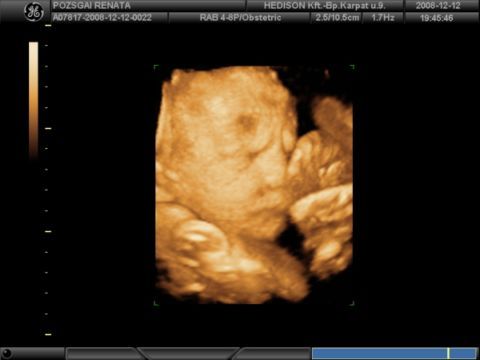

mezsó, kis koboldra hasonlít vmiért Noli